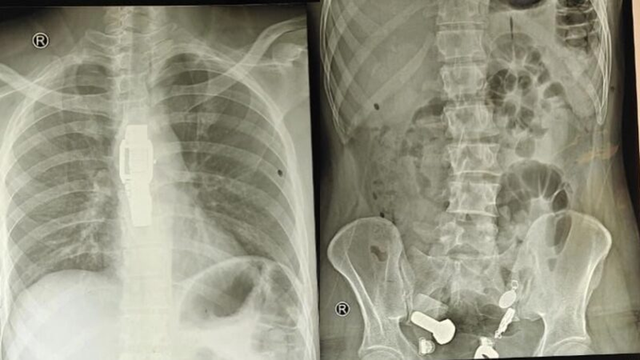

Một người đàn ông ở Ấn Độ gần đây đã nhập viện vì đau dạ dày dữ dội, khiến anh ta khó ăn. Ban đầu, các bác sĩ nghi ngờ đây chỉ là một vấn đề tiêu hóa đơn giản, nhưng kết quả chụp X-quang cho thấy một vật thể lạ bên trong cơ thể anh ta.

Theo báo cáo, nam bệnh nhân nhân này đã được gia đình đưa đến Bệnh viện Sawai Mansingh ở Jaipur, Ấn Độ sau khi bị đau bụng dữ dội và cực kỳ yếu do không thể ăn uống bình thường.

Sau khi thăm khám và chụp X-quang, các bác sĩ thấy một chiếc đồng hồ đeo tay, bu lông và ốc vít, được gắn chặt vào nhau... trong bụng bệnh nhân.